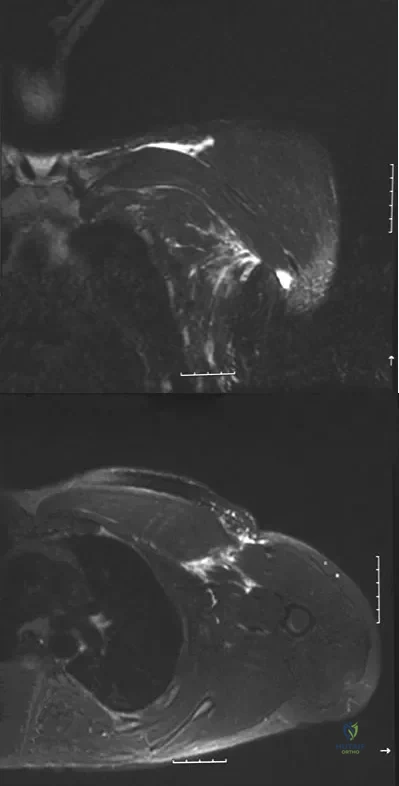

A 38-year-old left hand-dominant bodybuilder reports ecchymosis in the left axilla and anterior brachium after sustaining an injury while bench pressing 3 weeks ago. Coronal and axial MRI scans are shown in Figures 16a and 16b. What treatment method yields the best long-term results?

Explanation